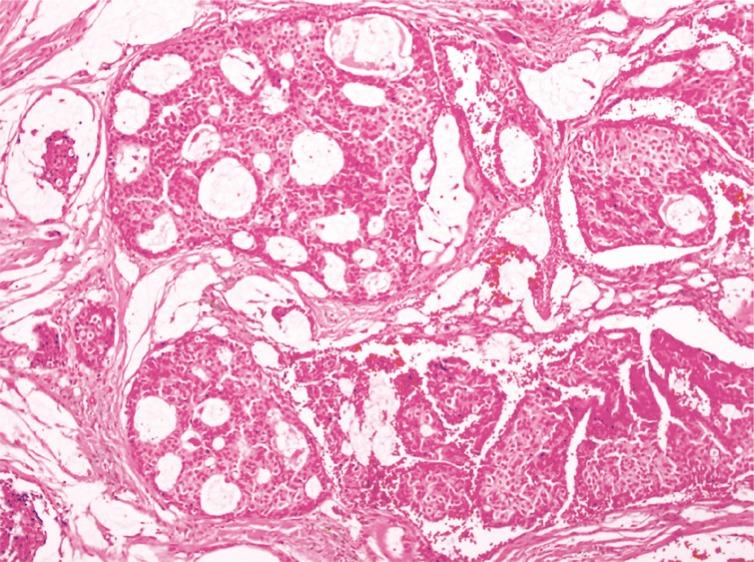

Primary cutaneous mucinous carcinoma (PCMC) is a rare malignant tumor of eccrine origin. Clinically, the carcinoma presents as a solitary, slow growing, and painless nodule. For this reason, this tumor is often considered to be a benign mass in the preoperative setting. The lesion is, however, malignant in nature and has a tendency for local recurrence and infrequent metastasis. Wide local excision is the treatment of choice. However, few reports exist with information regarding surgical margins and clinical outcomes. Herein, we report a case of PCMC excised with a narrow surgical margin and review the relevant literature. A 49-year-old man presented with a small cutaneous nodule of the right cheek. The mass was excised without any margin, but pathologic examination revealed histology of mucinous carcinoma. Because of this, the operative site was re-excised with a 5-mm margin, and the wound was closed using a V-Y advancement flap. Systemic work-up did not reveal other potential metastatic primary, for a final diagnosis of PCMC. We report this case of PCMC, treated with relatively narrow margin in a patient with good prognostic factors.